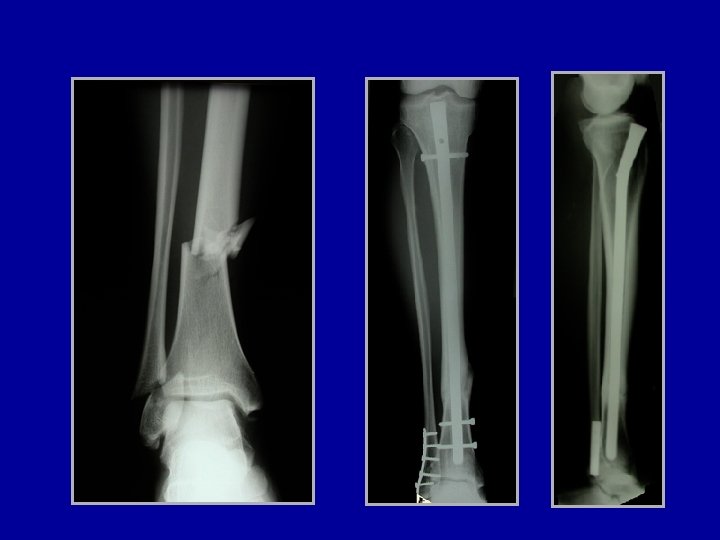

Cas particulier des fractures métaphysaires ouvertes Les broches sont difficiles à placer dans une épiphyse

Cas particulier des fractures métaphysaires ouvertes Les broches sont difficiles à placer dans une épiphyse Fixateur de Sheffield

Cas particulier des fractures métaphysaires ouvertes Ostéosynthèse a minima de l’épiphyse et de la métaphyse et mise en place d’un fixateur à distance

Cas particulier des fractures métaphysaires ouvertes Ostéosynthèse a minima de l’épiphyse et mise en place d’un fixateur. Quand le péroné est déplacé, une plaque est possible si la peau est intacte en dehors En cas de perte de substance osseuse, on fera une greffe secondairement

Cas particulier des fractures métaphysaires ouvertes